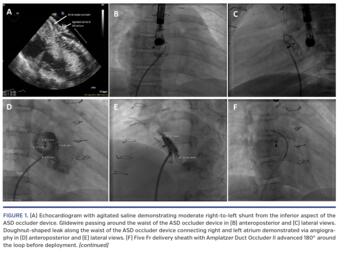

A 10-year-old girl with pulmonary atresia status post transannular patch repair and secundum atrial septal defect (ASD) underwent percutaneous ASD closure with 14 mm Amplatzer ASD occluder (ASDO; Abbott Vascular) at the age of 5 years. There was improvement in arterial saturation from 86% to 98% with minimal residual right-to-left shunt. She subsequently developed recurrent migraines despite medical therapy. Echocardiogram with agitated saline (EAS) demonstrated moderate residual right-to-left shunt from the inferior aspect of the ASDO (Figure 1A). After extensive discussion, we elected to pursue percutaneous closure of the right-to-left shunt due to her recurrent migraines.

Cardiac catheterization was performed via femoral approach and revealed a right atrial pressure of 10 mm Hg with a pulmonary to systemic blood flow ratio of 0.9. Multiple attempts were made to advance wires into the left atrium along the ASDO without success. However, each wire passed around the waist of the ASDO in a circular fashion (Figures 1B and 1C; Video 1). After advancing the wedge catheter along the wire, angiography revealed a “doughnut-shaped” leak in a 360° loop along the waist of the ASDO connecting the right and left atrium (Figures 1D and 1E; Video 2). We elected to close this channel using a 6 x 6 mm Amplatzer Duct Occluder II (ADO2). A Glidewire (Terumo Medical) was advanced along the waist into the left atrium and the Glide catheter (Terumo Medical) was advanced into the left atrium. Several wires were used to secure the position; however, we could not advance the 5 Fr Flexor delivery sheath (Cook Medical) across the full loop due to high tortuosity within the ASDO. Therefore we advanced the ADO2 180° around the loop and deployed the device (Figure 1F; Video 2). Repeat angiogram showed complete occlusion with no right-to-left shunt (Figures 1G and 1H; Video 2). The device was released and repeat EAS confirmed no residual shunt. The patient subsequently had near complete resolution of her migraines.